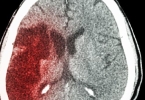

治疗脑供血不足可通过调整生活方式、控制基础疾病、药物治疗、手术治疗及康复训练等方式改善。脑供血不足通常由动脉粥样硬化、高血压、颈椎病等因素引起,表现为头晕、头痛、视物模糊等症状。

颈动脉内膜剥脱术适用于颈动脉狭窄超过70%的患者。血管内支架成形术可用于椎动脉或锁骨下动脉狭窄病变。术后需长期服用氯吡格雷片等抗血小板药物,预防支架内再狭窄。手术前后需严格控制血压和血糖。

脑供血不足患者应定期监测血压、血糖、血脂等指标,每3-6个月复查颈动脉超声或经颅多普勒。饮食以地中海饮食模式为主,多摄入深海鱼、坚果、橄榄油等富含不饱和脂肪酸的食物。避免突然转头或体位改变,沐浴水温不宜过高。若出现肢体麻木无力、言语不清等卒中先兆,须立即就医。